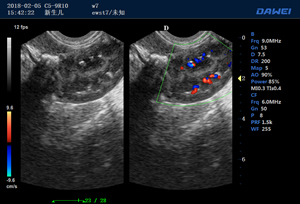

·支持B、C、PW、CW、寬景成像